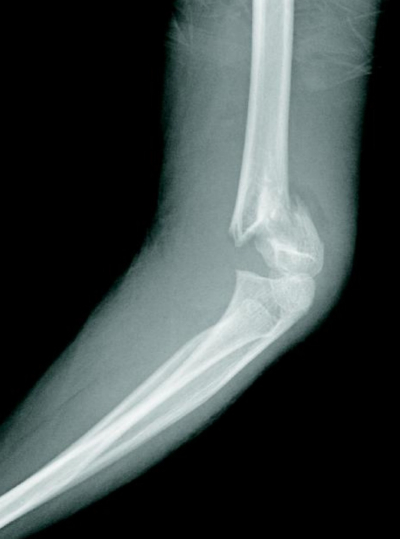

9歳の男児。左肘痛を主訴に母親とともに来院した。自転車乗車中に転倒し、左手をついて受傷した。左肘関節エックス線写真を別に示す。徒手整復を行う準備をしていたところ、左前腕部にも疼痛が出現し、左手指の自動運動が不能となった。